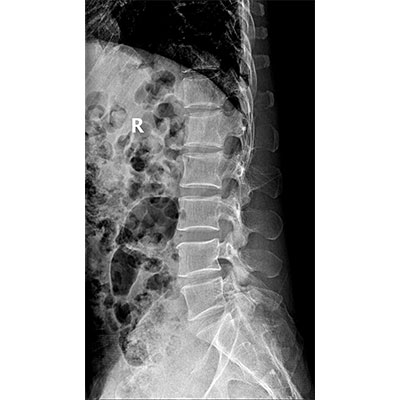

以微知形 為愛(ài)負責 微劑量 極速曝光 PLX8500E/F

● 采用自主研發(fā)的技術(shù),在保證優(yōu)質(zhì)圖像的前提下,大大降低X射線(xiàn)劑量,用心呵護醫護工作者及患者的健康。

● 短曝光時(shí)間,便于老年人、兒童、殘疾人進(jìn)行臨床拍攝。避免這類(lèi)群體因不能有效控制身體運動(dòng)等因素造成的運動(dòng)偽影,提高攝片質(zhì)量及效率。